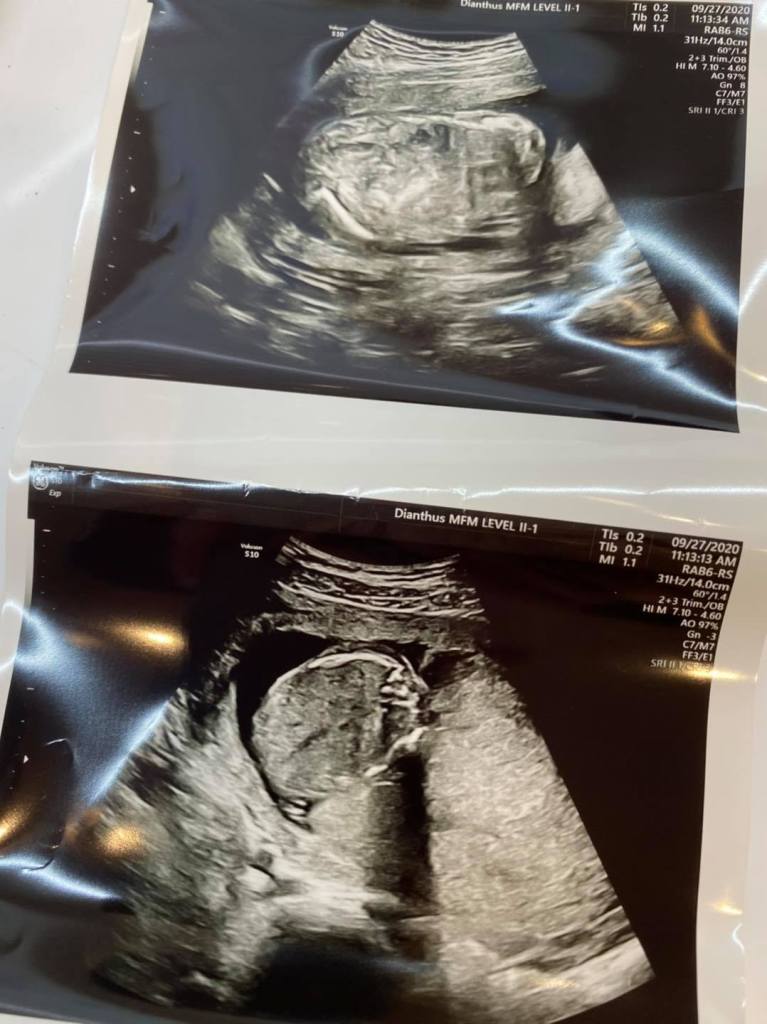

對很多人來說

這是一張再平凡不過的19週超音波照片了

甚至

切面還不標準呢

但因為媽咪肚子上還有小傷口

為了不影響復原

所以只能簡單照一下

但重點是

兩天過去

寶寶膀胱的尿液也全順利排空了

媽咪可以暫時出院回家休息